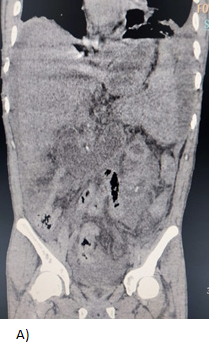

A 27-year-old male with a history of multiple hospitalizations and transfusions for dengue hemorrhagic fever, HIV (+) seven years ago with self-suspended treatment five months ago. He went to the emergency room due to abdominal pain in the epigastrium of three weeks' evolution accompanied by hyporexia, asthenia, and adynamia with hematochezia on one occasion, vomiting coffee grounds on one occasion with respiratory difficulty and dyspnea, denying fever or cough. Physical examination revealed moderate dehydration, pale integuments, tachypnea, and wheezing in the left hemithorax with wheezing in the right hemithorax, abdomen with signs of peritoneal irritation, vital signs: BP 100/60 mmHg, HR 154/min, Breaths 28/min, temp. 36.8 °C. Diagnosis of probable community-acquired pneumonia plus upper gastrointestinal bleeding, severe dehydration and HIV, hypovolemic shock, and septic shock are included. Laboratories: hemoglobin 5.5g/dL, leukocytosis (31000/103/L, absolute neutrophils 28 302/103L, lactic acidosis (PCO2 20.300 mmHg, PO2 73.40mmHg, HCO3 11.50mEq/L and lactate 12.60mmol/L). Tomography with data of honeycombing in both lungs to rule out PTB vs. PCP (Pulmonar tuberculosis vs. Probable Candida parapsilosis), left pleural effusion, bilateral atelectasis, and free peritoneal fluid with suspicion of probable gastric perforation. A CT scan is performed without specifying the origin of the septic shock (Figure 1 & 2). The patient is admitted to the operating room for exploratory laparotomy, purulent fluid (2500ml) is aspirated, a splenic abscess is identified on the diaphragmatic side and splenectomy is performed with the standard technique, admission to the Register Intensive Care Unit, later to the general surgery floor with an in-hospital stay of 9days, he is discharged with control by internal medicine, surgery and SAIH (Hospital Comprehensive Care Services).

Figure 2 Photomicrographs with a diagnosis of perisplenic abscess and plasmatic cell infiltrate of the parenchyma.